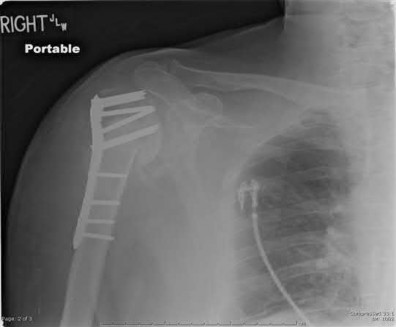

Figures A-C are the radiographs of a 26-year-old male who presents to the emergency department following a motocross accident. Two attempts at a closed reduction by the on-call orthopedic resident were unsuccessful. Figures D and E are the pre-operative axial CT-images that were obtained. The patient undergoes surgical fixation seen in Figure F. Limitations in post-operative dorsiflexion is likely influenced by which of the following?

The rare Bosworth fracture-dislocation is a posterior dislocation of the fibula which becomes entrapped behind the tibia. As demonstrated in this vignette, these injuries are extremely difficult to close reduce secondary to the ridge of the posterolateral distal tibia. The irreducible nature of this injury is a known risk factor for the development of compartment syndrome. The CT images further demonstrate fracture extension to the posteromedial rim (“posterior pilon variant”). In this situation, the only effective method to reduce the fracture is through an open posterolateral approach with the interval between the flexor hallucis longus and the peroneal tendons. This is the same approach that is utilized for fixation of the posterolateral fragment and fibula. Loss of dorsiflexion has been demonstrated following this fracture pattern with posterior fixation. The positioning of the plates in Figure F suggests the

utilization of a posterolateral approach.

Figures A-C: The initial radiographs reveal the posterior subluxation of the talus with associated posterior subluxation of the fibula without significant coronal plane deformity. This deformity should raise the suspicion of a Bosworth fracture-dislocation, especially if closed reduction is not successful. Figures D and E: Axial CT images demonstrating Bosworth fracture-dislocation of the fibula entrapped behind the tibia. Also, note the fracture extension to the posteromedial rim in this posterior pilon variant.

Figure F: Positioning of the plate suggests a posterolateral approach to address both the fibula and posterior malleolus fractures.